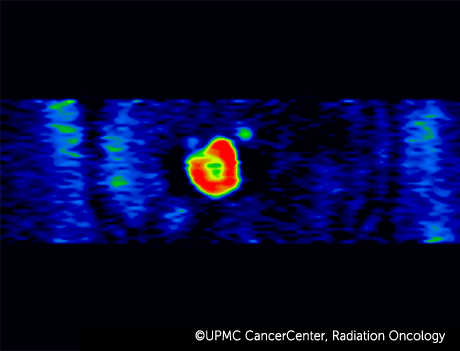

4D PET-CT combines positron emission tomography (PET) with computed tomography (CT) to take advantage of these faster, more accurate technologies.

- Captures the movement of your organs and tumor over time, while also recording the metabolism of the tumor.

- Makes it possible to see the makeup and function of your tumor.

By understanding the functional and material aspects of the tumor, your radiation oncologist can conclude which parts of the tumor need more (or less) radiation for more effective treatment.